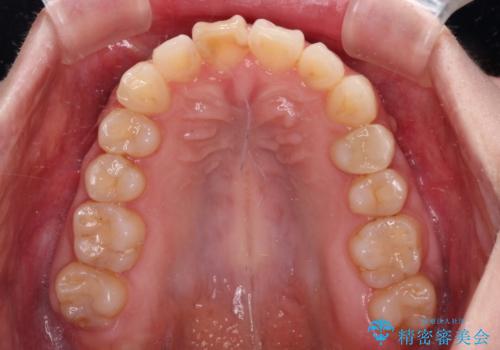

- 上顎前歯の突出感と、前歯のクロスバイトを気にして来院された患者様です。

前歯の叢生と口元の閉じにくさを気にして来院された患者様です。

奥歯の咬み合わせを見ると、上顎が下顎に対して相対的に前方にありました。

口元の閉じにくさを改善するためには、上顎臼歯を後方に移動させた咬み合わせにする必要があります。

インビザライン単体で改善することも可能ですが、達成する可能性が高くないため、カリエールディスタライザーという補助装置を併用して、より確実性を上げることとしました。

奥歯の咬み合わせを改善しながら、並行してインビザラインで歯列を整えることとしました。

カリエール・ディスタライザーを用いたことで上顎前歯の突出感はスムーズに解消され、歯列不正は1年半ほどでほぼ改善することができました。

しかし、その後インビザライン特有の奥歯がうまく噛めないという問題が長引き、改善に1年近い期間を要することとなりました。